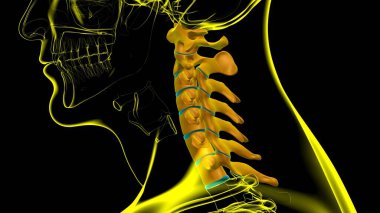

İnsan İskeleti Omurgası Servikal Omurga Anatomisi 3D İllüstrasyon

İnsanTıbbiparmakBoyunomurgaKalçaRADIUSsakralGöğüs kemiğiskapulaLeğen kemiğitorasikçene kemiğiparietallombersakrumTibiaUyluk kemiğiKöprücük kemiğisokumupazı kemiğidirsek kemiğioksipitaldiz kapağıkemikler3d oluşturmaGöğüs kafesiüst ekstremiteOmurga SütunuAyak bileği Ağrısıbel kemiğiayak kemikleriiskelet anatomisidiz eklem ağrısıservikal bölgeclavicle bonewrist carpalscervical vertebrae anatomyBenzer İçerikler